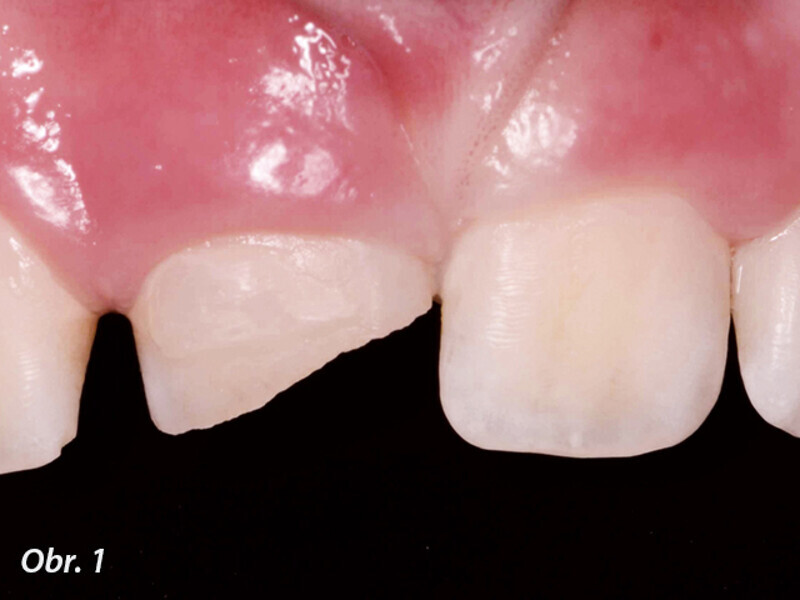

Endodontické ošetření horního středního řezáku s atypickou anatomií